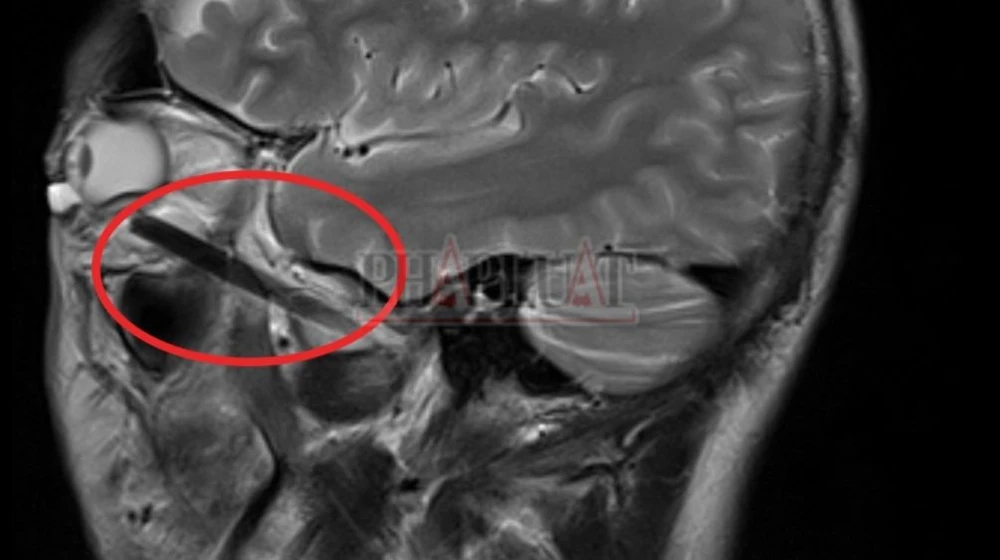

Hình ảnh chụp MRI mới phát hiện một phần chiếc đũa đâm sâu trong hốc mắt.

Theo bác sĩ của bệnh viện đa khoa tỉnh Bình Dương, anh TNB có triệu chứng nhức mắt nên đến bệnh viện thăm khám. Tại đây, các bác sĩ tiến hành chụp MRI mới phát hiện một phần chiếc đũa dài khoảng 6 cm nằm sâu trong hốc mắt anh B.